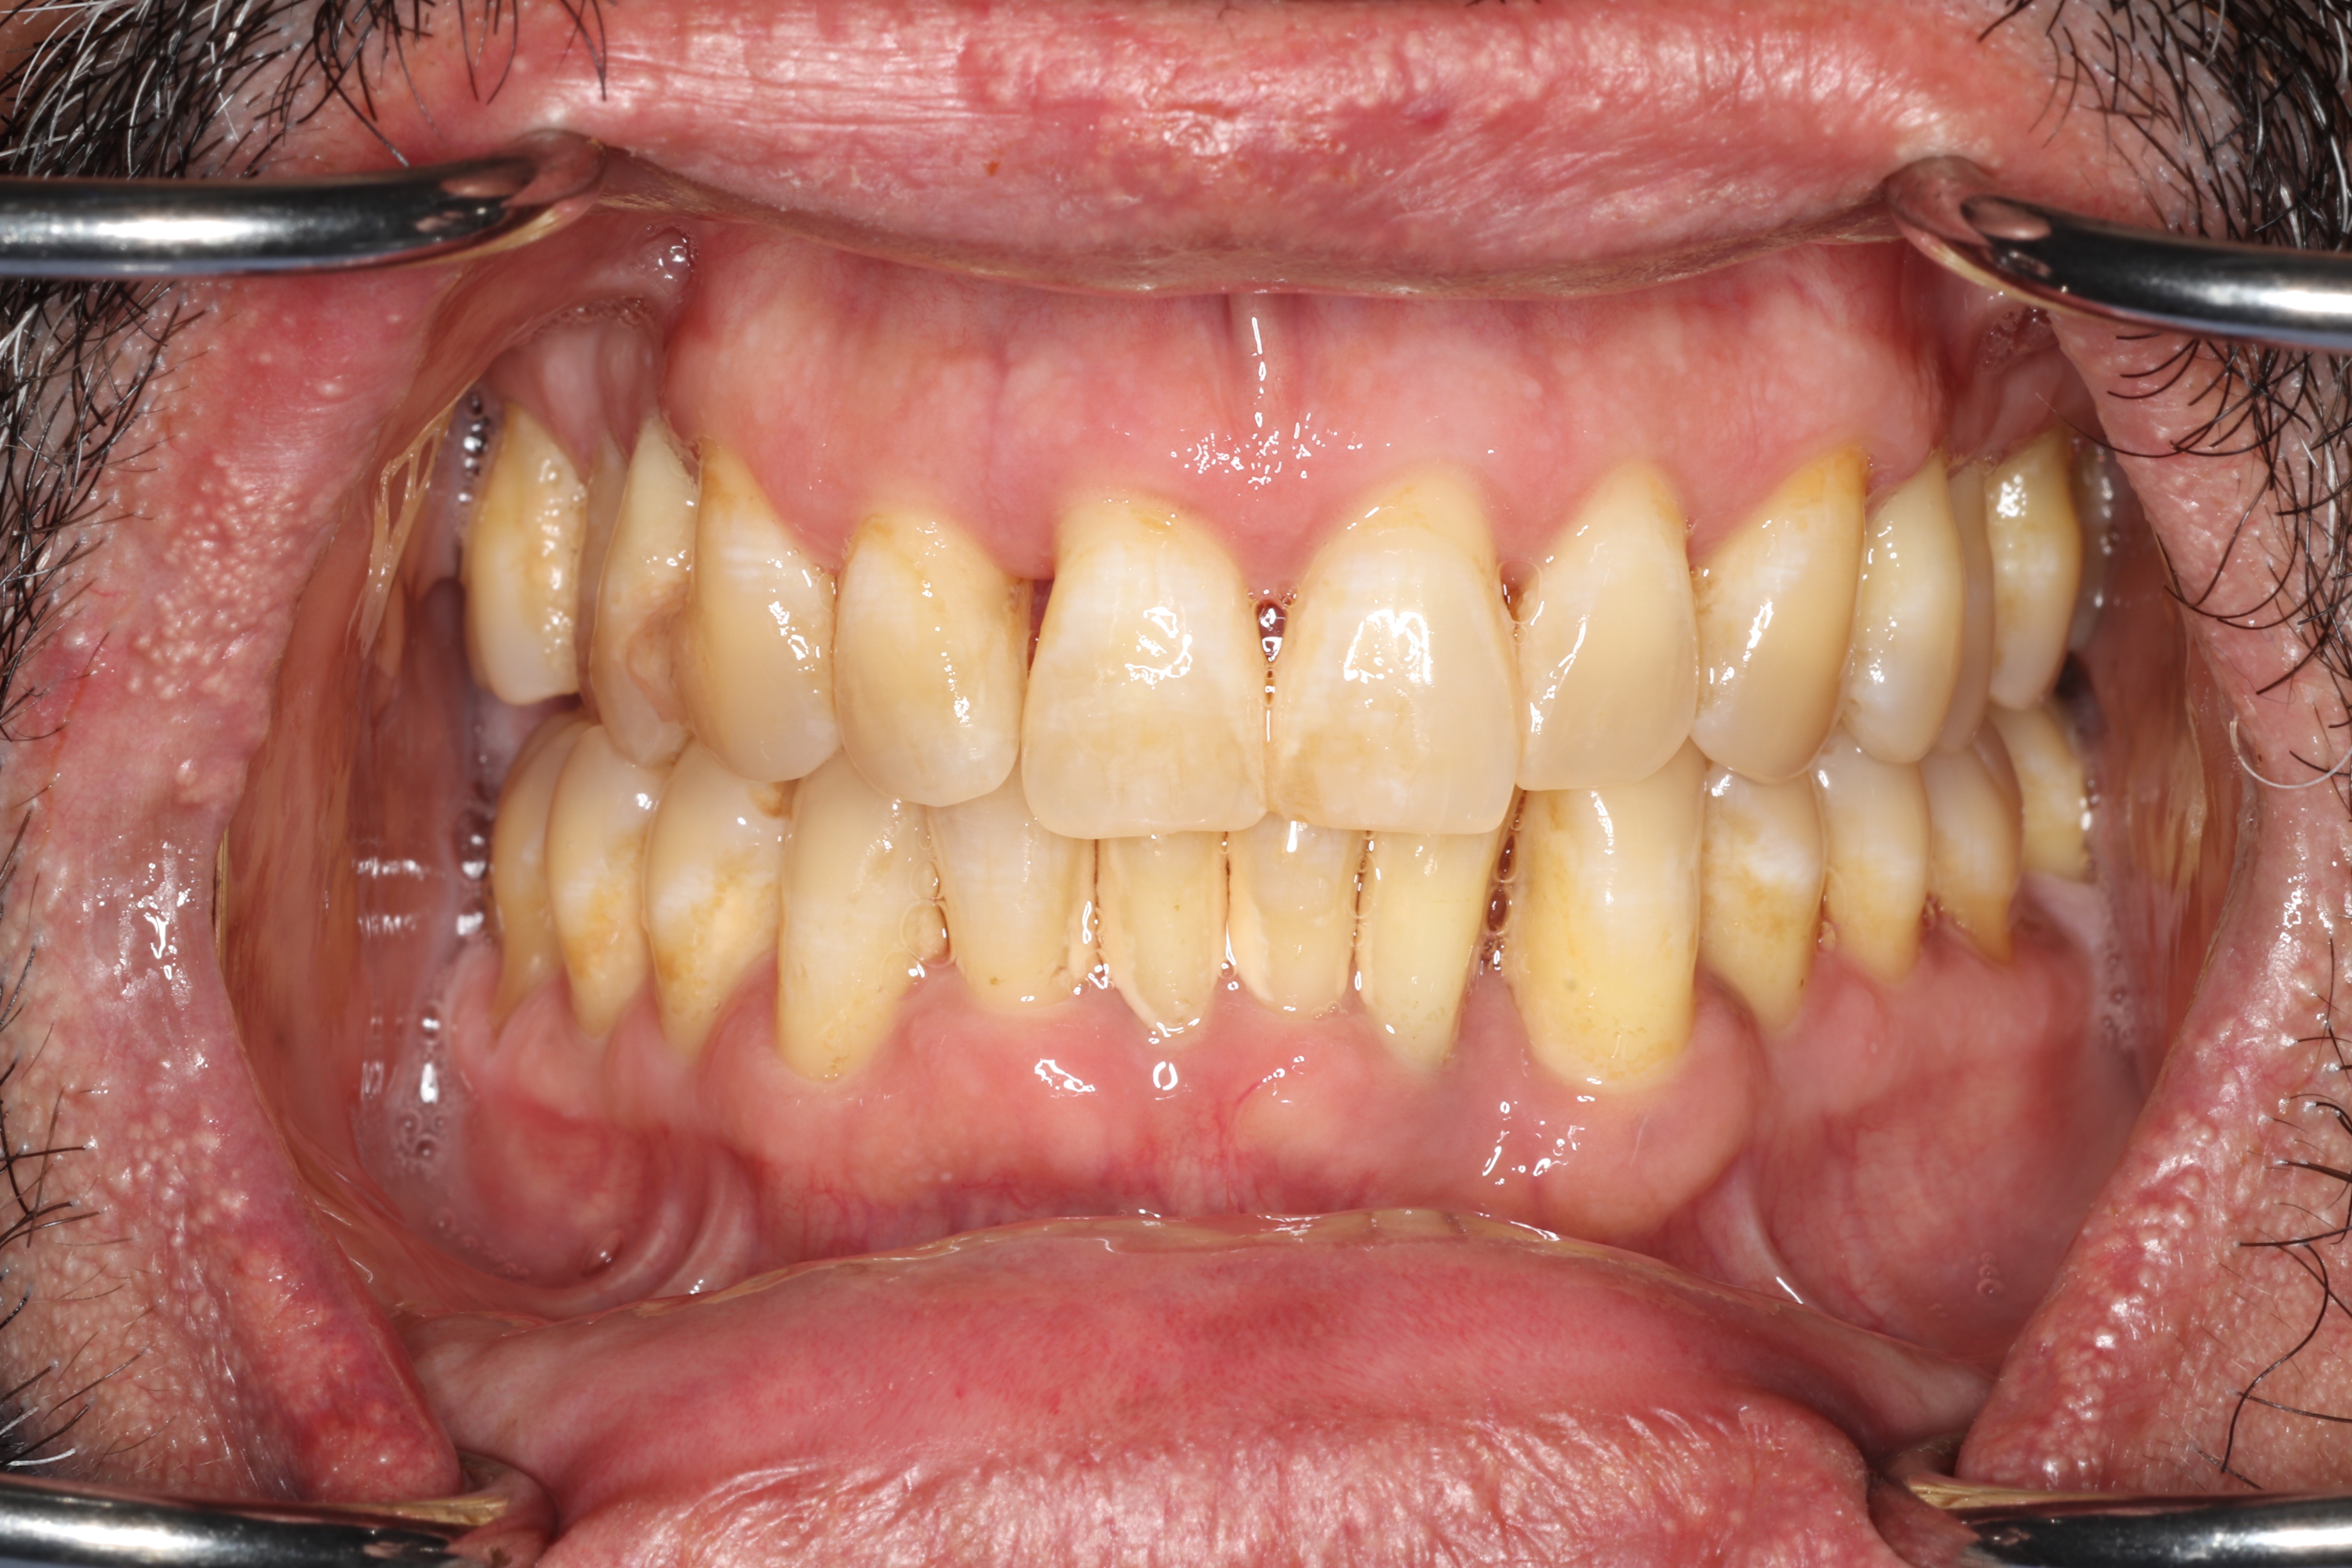

Effects on Your Mouth

As bone is lost, you may notice teeth feeling looser, teeth shifting position, gaps developing where teeth used to be tight together, food getting stuck in new places, difficulty chewing, and increased sensitivity as root surfaces become exposed. Gum recession can change the appearance of your smile. In advanced cases, painful infections (periodontal abscesses) can develop within deep pockets. Without treatment, the end result is tooth loss.

- Probing Depths: We gently measure the depth of the space between your gum and each tooth. In health, this pocket measures 1 to 3 mm. At this depth, bacteria can be 100% removed during cleanings and you can keep the area clean at home. Pockets of 4 to 5 mm are "borderline"; we can typically remove about 60 to 70% of bacteria, usually enough to stop bone loss, though these sites need close monitoring. Pockets of 6 mm or deeper are at severe risk, as most bacteria cannot be reached non-surgically.

- Bleeding on Probing: Healthy gums do not bleed. Bleeding during probing tells us active inflammation is present. Important for smokers: nicotine constricts blood vessels, so gums may not bleed even when disease is active.

- X-Rays (Radiographs): X-rays show the pattern and extent of bone loss. We can see whether bone has been lost evenly (horizontal loss) or whether craters and vertical defects have formed. This pattern directly determines which type of treatment you need.